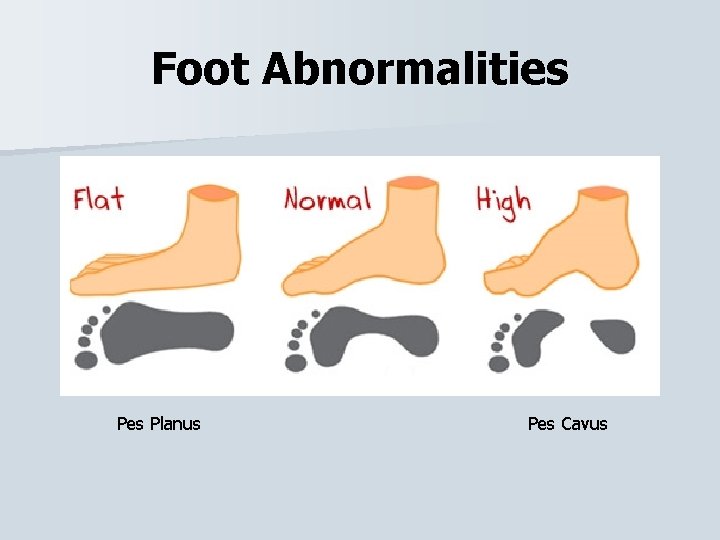

Foot Abnormalities Planus Pes Cavus